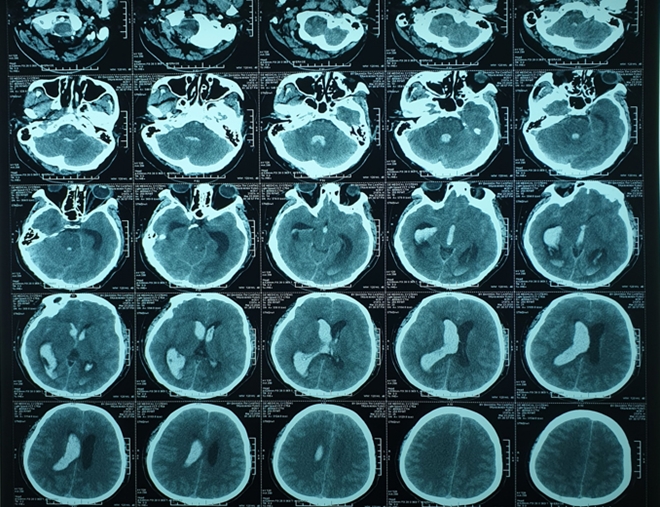

Kết quả chụp cắt lớp vi tính (CLVT) sọ não cho thấy bệnh nhân bị chảy máu não tràn vào hệ thống não thất, gây dãn toàn bộ hệ thống não thất.

Hình ảnh chụp cắt lớp vi tính não bệnh nhân trước mổ.

Kết quả CLVT sọ não kiểm tra sau mổ cho thấy hệ thống não thất đã bớt giãn nhưng vẫn còn tụ máu nhiều, khả năng tắc ống dẫn lưu là rất cao. Ê kíp BS tiếp tục bơm thuốc tiêu sợi huyết vào não thất thông qua ống dẫn lưu kết hợp theo dõi áp lực nội sọ liên tục.

Kết quả ngoài mong đợi của các BS, CLVT tuần thứ nhất sau mổ cho thấy máu tụ trong não thất giảm đáng kể, bệnh nhân tri giác cải thiện, giảm sốt, được rút ống dẫn lưu não thất.

Và hình ảnh sau mổ.